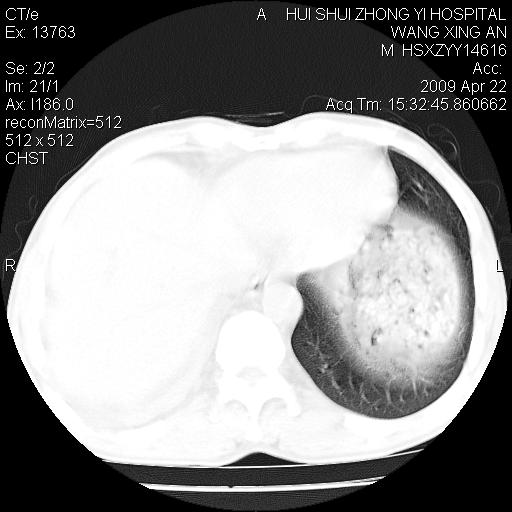

标题: CT19534:患者男、46岁咳嗽、胸痛半月。 [打印本页]

标题: CT19534:患者男、46岁咳嗽、胸痛半月。

中央型肺癌,右侧腹水

考虑---右肺中心型肺癌继发下叶不张,少量胸水。

支持右侧中央型肺ca并右下肺不张、右侧胸腔少量积液。

1、右下肺中央型肺癌并右肺转移,右肺下叶不张。(右肺有结节影)。

3、右侧胸腔积液。

1、右下肺中央型肺癌并右肺转移,右肺下叶不张。(肿块围绕右肺下叶支气管生长,致管腔闭塞右肺下叶不张;右肺有结节影)。

2、右侧胸腔积液。

1)右肺中间段支气管癌并右肺下叶肺不张。2)右肺上叶、两肺下叶背段感染性病变。3)右侧少量胸腔积液。